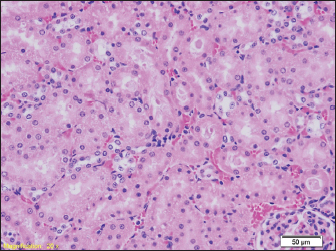

Signs of hydropic and vacuolar degeneration can be seen in the kidney samples of all groups of rats, and signs of acute tubular necrosis can be seen in one of the samples (group G2) (Figs. 7 and 8).

Fig. 7. Kidney parenchyma also shows signs of congestion (HE, ×40). Signs of hydropic and vacuolar degeneration can be seen in the kidney samples of all groups of rats, and signs of acute tubular necrosis can be seen in one of the samples (group G2) (Figs. 7 and 8).

Fig. 8. Signs of hydropic and vacuolar degeneration in epithelial cells of renal tubules (HE, ×200). Brain tissue samples of all groups of rats show a lower or higher degree of edema (Fig. 9).

Signs of hydropic and vacuolar degeneration can be seen in the kidney samples of all groups of rats, and signs of acute tubular necrosis can be seen in one of the samples (group G1).

The pathohistological findings of the kidneys in all examined groups indicate hydropic and vacuolar degeneration of the epithelial cells of the renal tubules, and the pathohistological findings of the brain in all groups show signs of pericellular and perivascular edema. In our study, we did not find diatoms in the kidneys. Previous studies prove that the number of diatoms found may be lower than expected, as in liver samples. Since the middle of the last century, there have been certain disagreements among numerous authors about the reliability of diatom findings in internal organs such as the kidney, liver, or bone marrow. The reason for this is the high rate of occurrence of false positive findings (Timperman, 1969).

The results of the pathohistological examination of the kidneys in our study coincide with those of other authors. In previous studies, after drowning, signs of glomerular enlargement with hypercellular changes were found on the kidneys, signs of degeneration were present in the tubules, such as their uneven expansion and edema of the cells of the tubular walls, and in the interstitium, there were congested capillaries were present (Ibrahim et al., 2022). Seong et al. (2012) also reported signs of acute tubular necrosis after drowning (Seong et al., 2012).